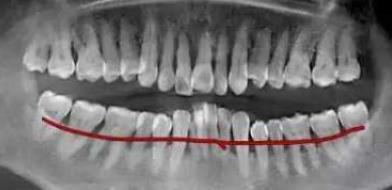

老年人,別看你的牙齒看著似乎沒有什麽(me) 鬆動,很穩固,但是其實牙齒周圍掌權的不是牙槽骨組織,看似這些牙結石把牙齒包裹起來形成一麵保護牆,其實是把牙齒封鎖起來,不讓人請以發覺。如果你不信,可以手掌半握,哈口氣看看有沒有口臭,如果有,那麽(me) ,你真的該洗牙了!

這樣牙槽骨萎縮嚴(yan) 重的牙齒名存實亡